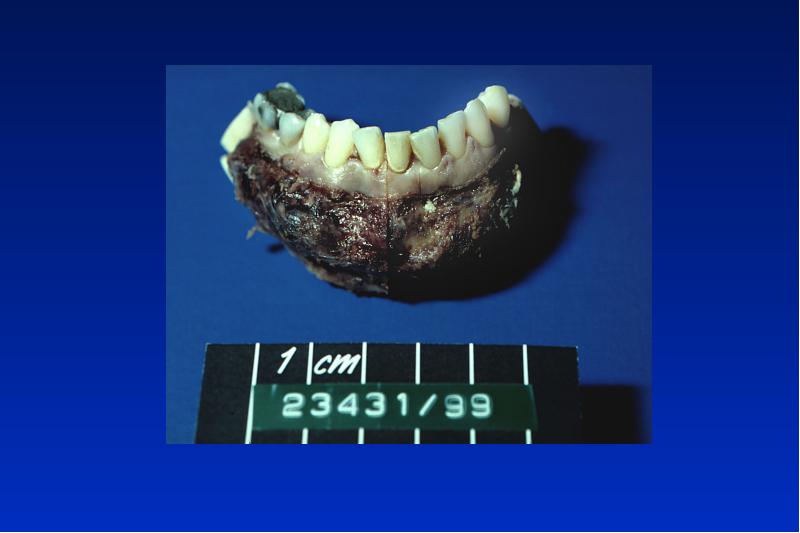

- 38. Ameloblastom solid intraössär/ peripher/unizystisch/ maligen benigner, lokal aggressiv wachsender Tumor

- 50. Kalzifizierender epithelialer odontogener Tumor (Pindborg Tumor) benigner lokal invasiver

- 56. Odontom complex = gemischt compound